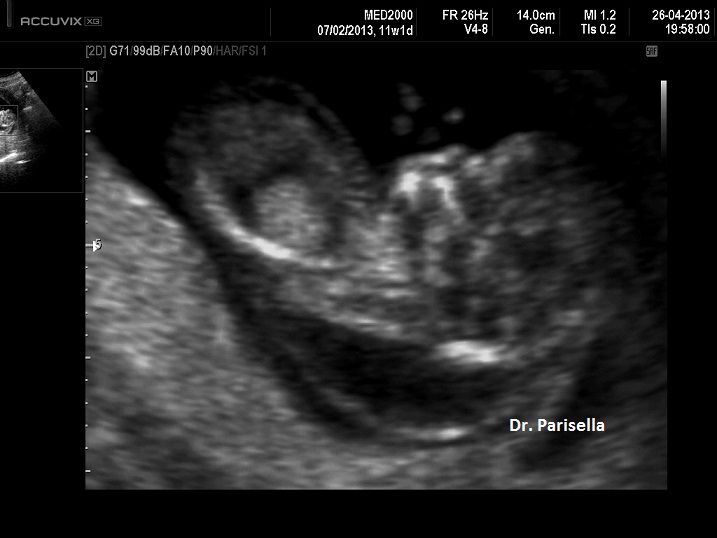

1) rilievo di SAF (assenza dei movimenti attivi fetali, dei movimenti dei muscoli respiratori e dei singhiozzi).